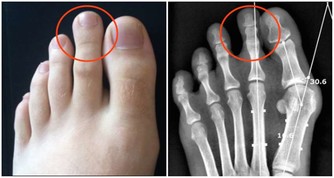

在我們的腎臟當中,腎小球有著過濾的作用,而腎小管能夠幫助吸收,但是隨著年齡的不斷增長,身體各項器官機能逐漸衰退,腎臟當中的這兩個零件也會逐漸老化,導致尿液濃縮濃度減退,從而出現這些問題。

如果在生活當中伴有慢性腎臟疾病的話,更會加速腎臟的萎縮,從而導致夜尿增多的現像明顯,但需要大家注意的是,並不是經常起夜就一定是腎功能發生問題,也有可能是心理或者生理因素導致的,還希望大家及時就醫檢查,查明原因做好針對性治療。